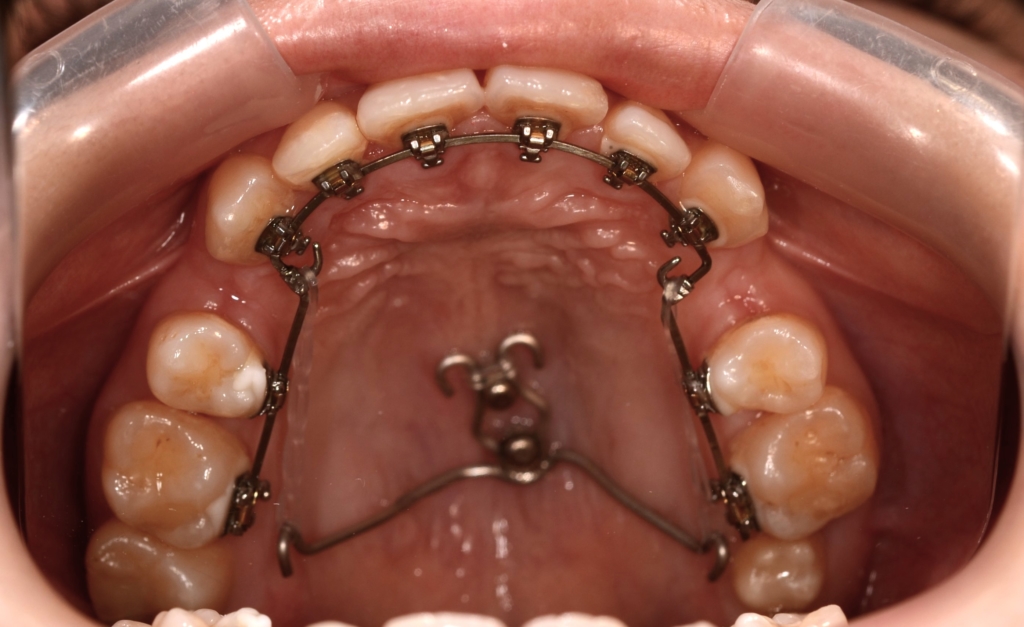

マルチブラケットシステム(ハーフリンガルtype)で矯正を開始。

アンカースクリューを2本使用

順当にステップが進んで、前歯を奥へ引っ込めるためのアンカースクリューを上顎の口蓋中央部分に植立します。

上下とも前歯を奥へ出来るだけたくさん引っ込めるように治療を進めます。